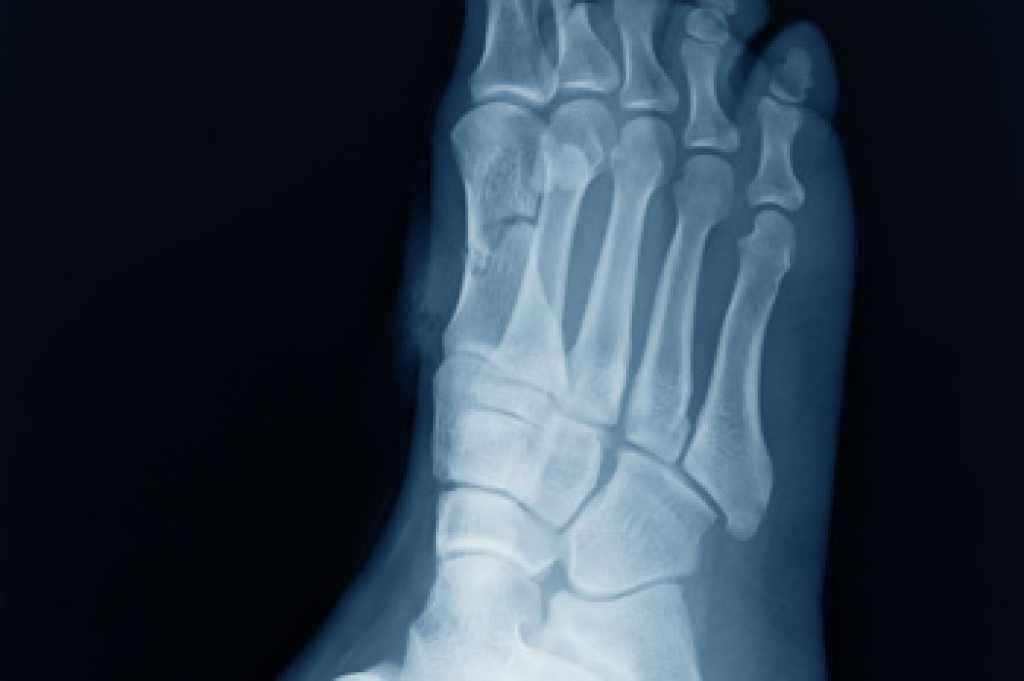

Achilles tendon injuries are diagnosed by a thorough physical evaluation, which can include an MRI. Treatment involves rest, physical therapy, and in some cases, surgery. However, various preventative measures can be taken to avoid these injuries, such as: